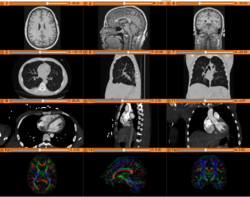

Slicer4 3D Visualization of DICOM images for Radiology Applications

- The 3D Visualization of DICOM images for Radiology Applications course guides through 3D data loading and visualization of DICOM images for Radiology Applications in Slicer4.5.

- Author: Sonia Pujol, Ph.D., Kitt Shaffer, M.D., Ph.D., Ron Kikinis, M.D.

- Audience: Radiologists and users of Slicer who need a more comprehensive overview over Slicer4 visualization capabilities.

- Modules: DICOM, Volumes, Volume Rendering, Models.

- Based on: 3D Slicer version 4.5

- The 3DVisualizationDICOM_part1 and 3DVisualizationDICOM_part2 datasets contain a series of MR and CT scans, and 3D models of the brain, lung and liver.